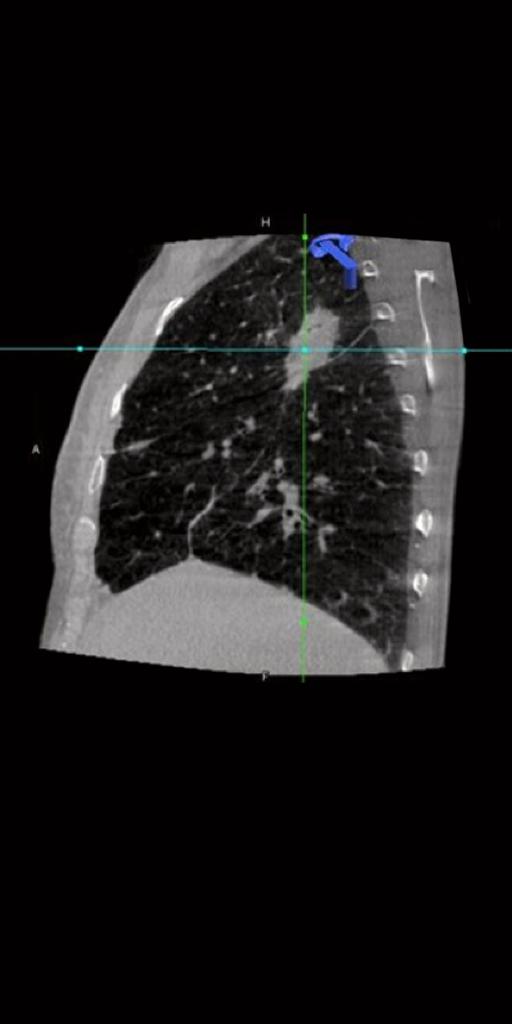

syngo Dyna3D

Confirmez le placement

de l’aiguille et de

la zone d’ablation avec syngo Dyna3D.

En imagerie pulmonaire, syngo Dyna3D

offre une excellente qualité d'image avec une dose réduite.1

par rapport à syngo

DynaCT.